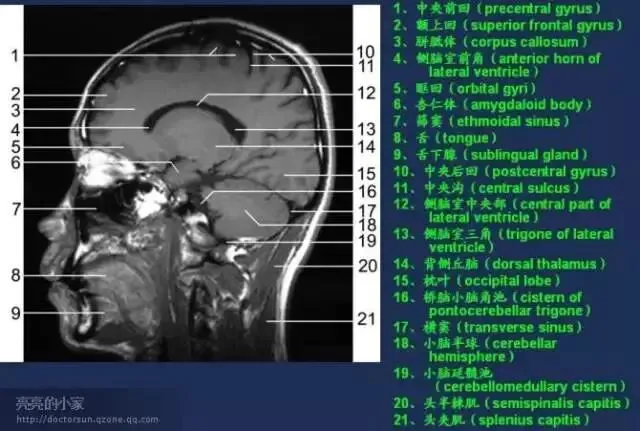

收藏!全身MRI解剖图谱,医生必备